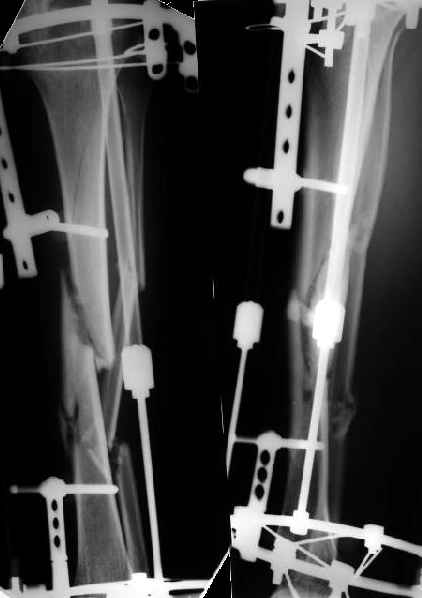

На голени - чрескожная остеотомия малоберцовой кости, закрытая остеоклазия большеберцовой, дистракционный остеосинтез аппаратом.

В плане - востановление длины и оси голени, разработка движеий в колене. Не уверен, что удастся синтезировать голень стержнем при таком маленьком сгибании в коленном суставе.